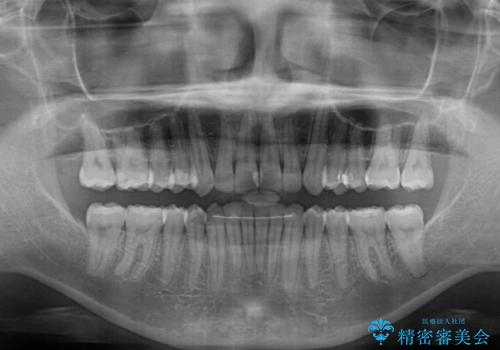

沖縄から飛行機で通院 インビザラインによる矯正治療

- 30代女性

- インビザライン

- 3年8ヶ月

- 定期的に東京に来るので、沖縄から矯正治療で通院したいとのことで来院された患者様です。

歯列不正は軽度であったので、応急処置の少ないインビザラインにて矯正治療を行うこととしました。

通院途中に、仕事の都合で東京に来る機会が激減してしまったため、なかなか治療が進まず、当初終了予定であった時期が2年近くずれ込んでしまいました。

今後もむし歯治療が必要となるため、日程を調整して沖縄から通院されるとのことでした。